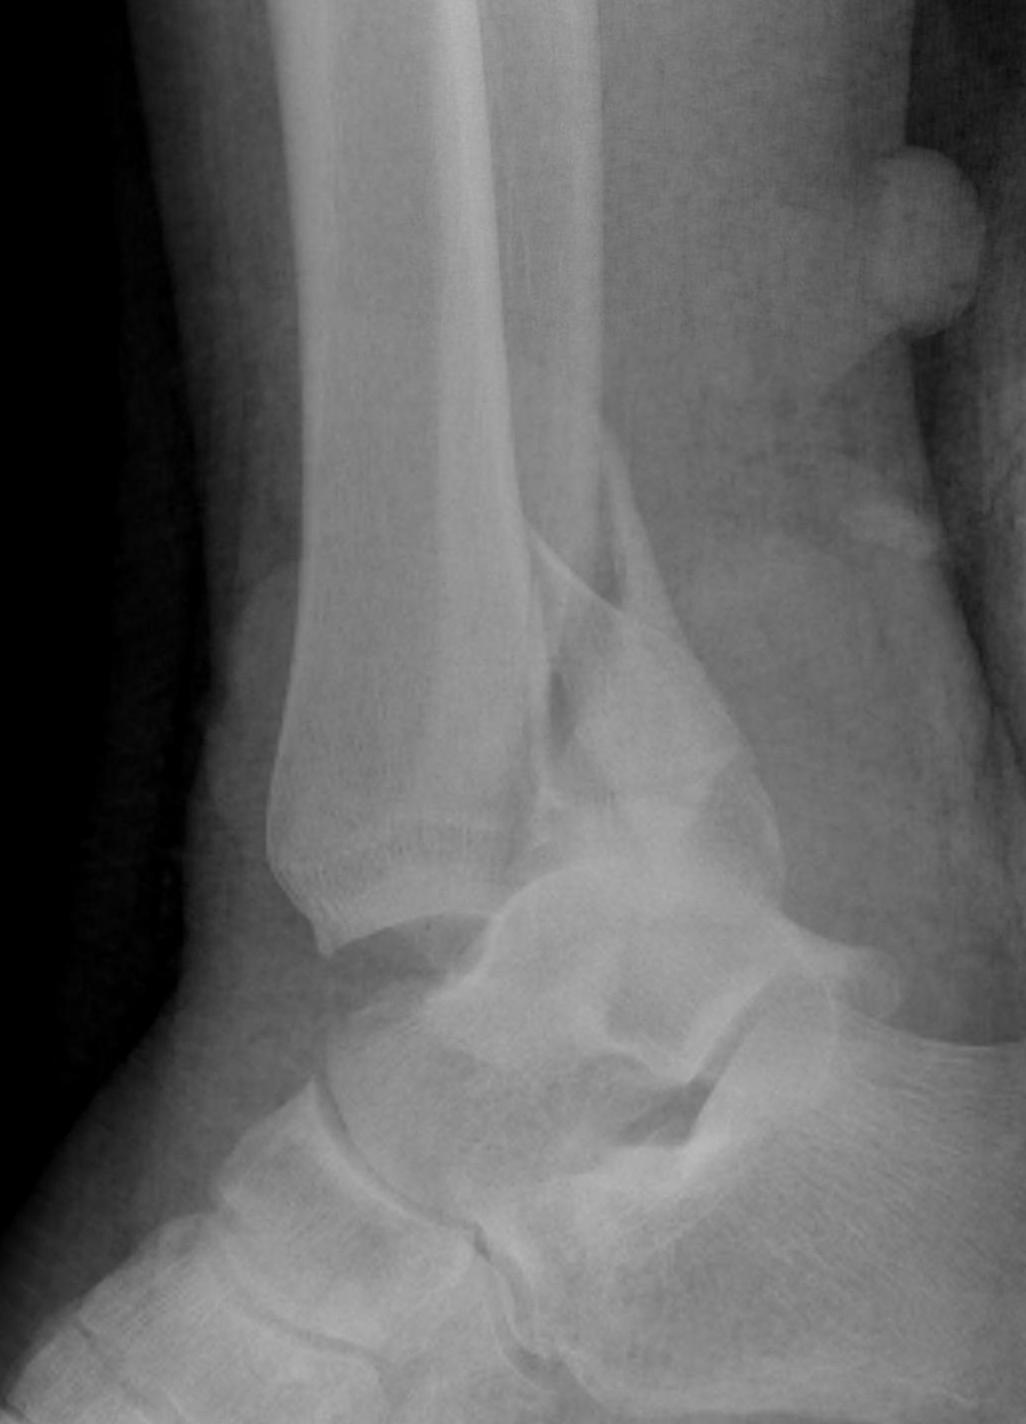

Lateral talar shift / increased medial clear space / deltoid ligament injury

Ankle Fracture Increased Medial Clear SpaceAnkle Fracture Increased Medial Clear Space 2Maisonnerve

Tibia / fibular overlap < 1mm / syndesmotic injury

Ankle Fracture Syndesmosis WidenedAnkle Diastasis